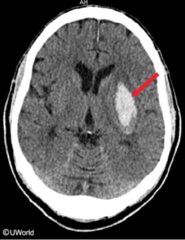

Lacunar infarcts

Front

hypertension affects deep penetrating arteries/arterioles supplying basal ganglia, deep white matter, and brainstem locations (in desc. order of freq.): lenticular nucleus, thalamus, internal capsule, deep white matter, caudate nucleus, pons single or multiple, small, cavitary infarcts <15mm

Back